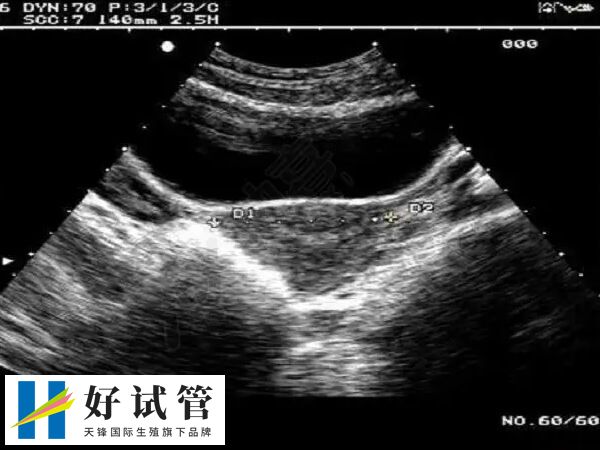

3、输卵管积水

输卵管积水的存在,会干扰到子宫内膜与胚胎的接触,影响胚胎的着床;输卵管积水临近卵巢,会对卵巢形成压迫作用,导致卵巢内的卵泡发育受到影响;输卵管积水对内膜的损伤往往是很大的,伤害子宫内膜的同时,还会加重宫腔的炎症,使宫腔环境进一步恶化。